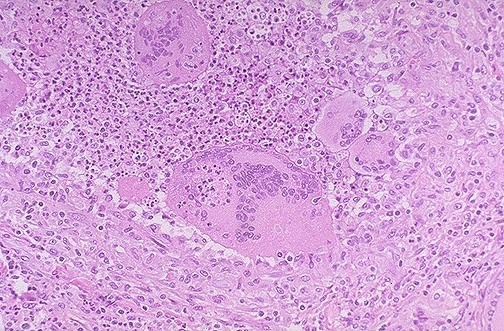

This is subacute granulomatous thyroiditis (DeQuervain disease), which probably follows a viral infection and leads to a painful enlarged thyroid. This disease is usually self-limited over weeks to months, with transient hyperthyroidism and/or hypothyroidism, and affected patients return to a euthyroid state. Note the presence of large foreign body giant cells with inflammatory destruction of thyroid follicles.